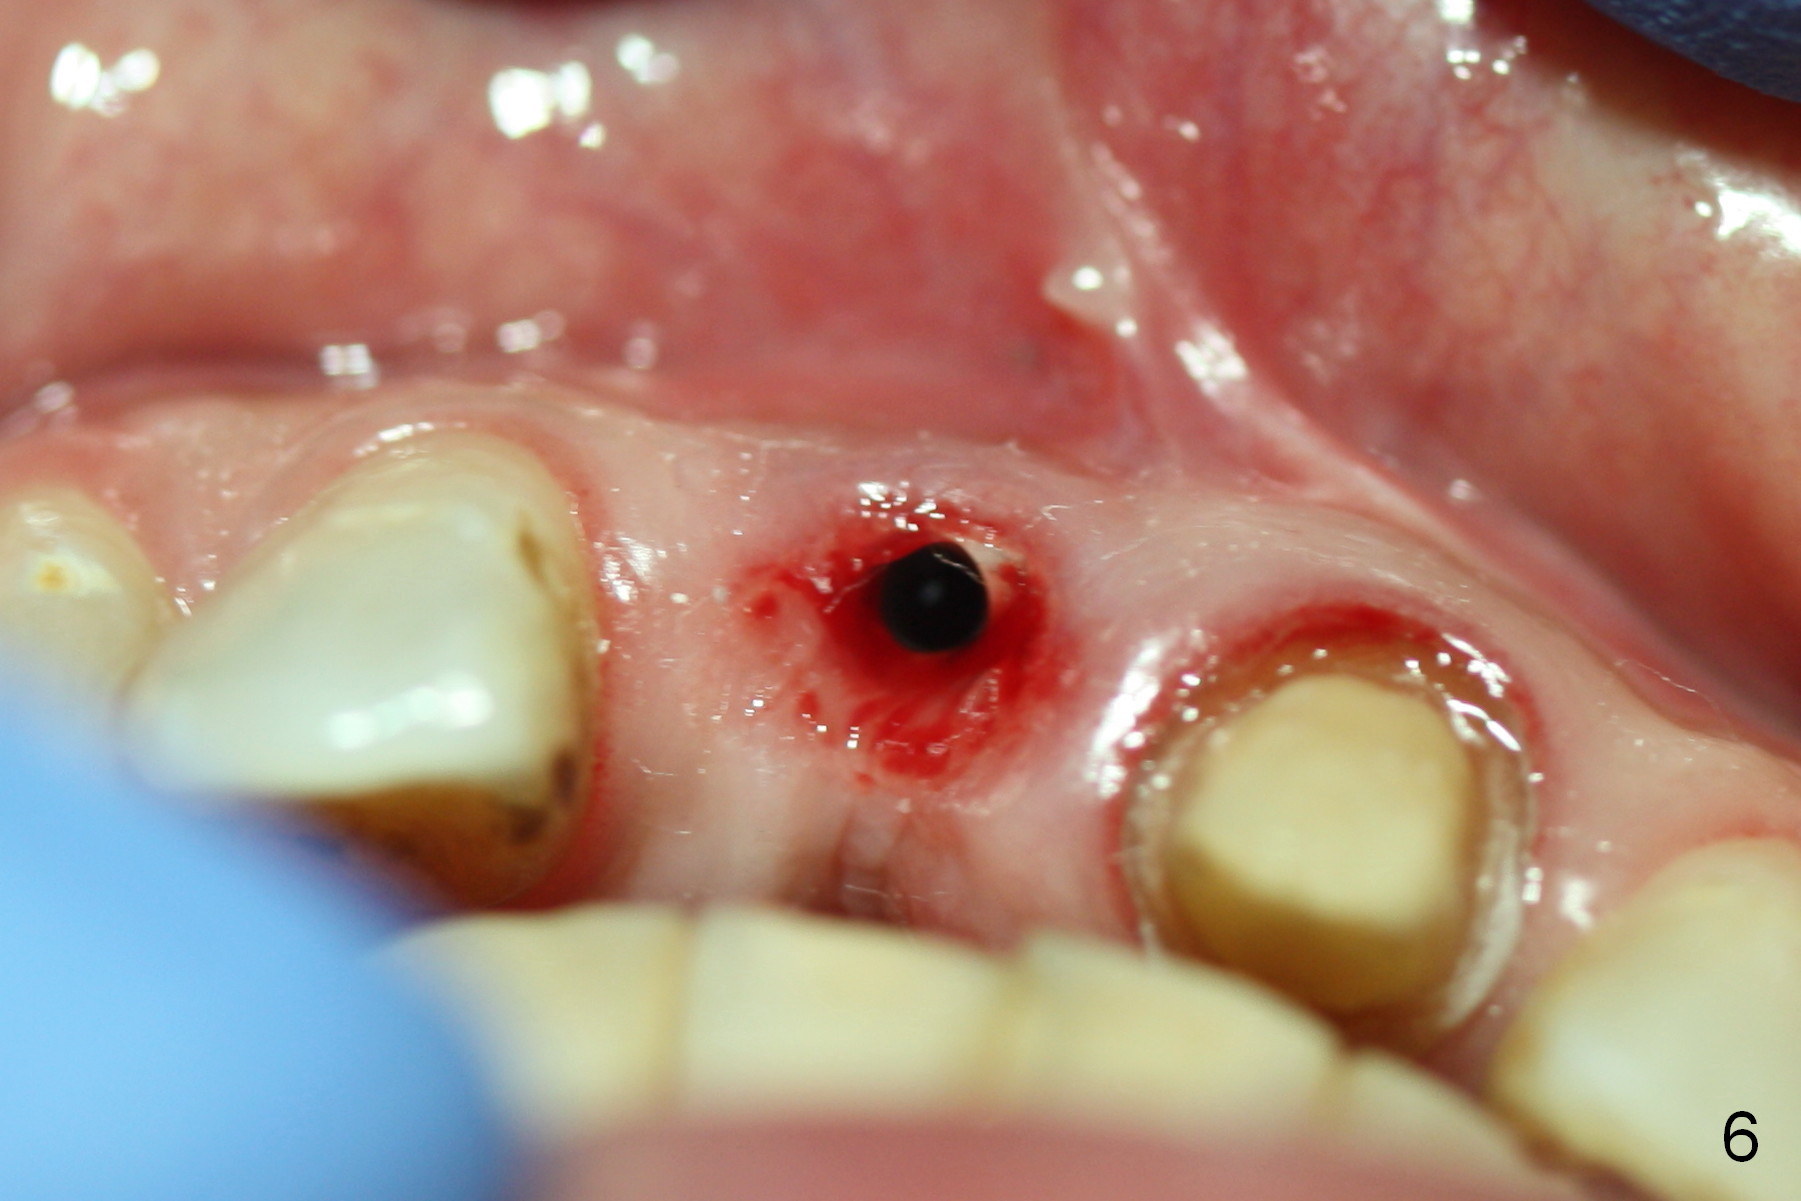

Fig.6,7 were taken a month ago when the Zirconium abutment was fractured, showing the position of the coronal end of the implant. To retrieve the abutment, an envelop incision will be made (Fig.8) with elevation of the buccal flap for the best visibility. Prepare abutment removing drivers (x3) and try in vitro. To improve cosmetics, the implant/bone segment seems to be required to be lingualized ~3 mm (Fig.9 arrow) with bone graft buccally (red circles, possibly chin graft).